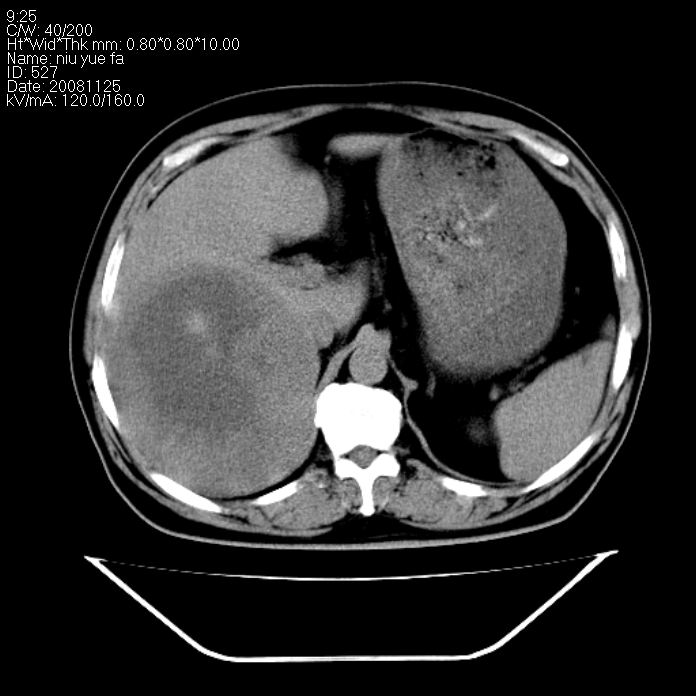

巨块型肝癌,坏死,出血;胆囊结石

1)考虑肝右叶巨块型肝癌并坏死、出血;建议行ct增强扫描检查进一步明确诊断。2)胆囊结石,胆囊炎。

考虑肝右叶巨块型肝癌并坏死、出血;建议行ct增强扫描。胆囊结石。

肝右叶巨块型肝癌并坏死、出血;胆囊结石,胆囊炎。